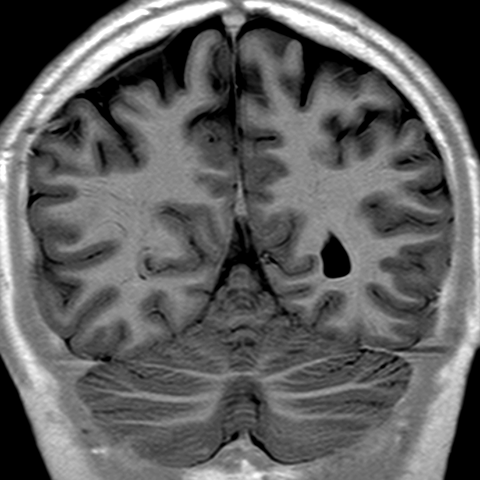

Cerebral Hemispheres, MR (normal) [8 of 9]